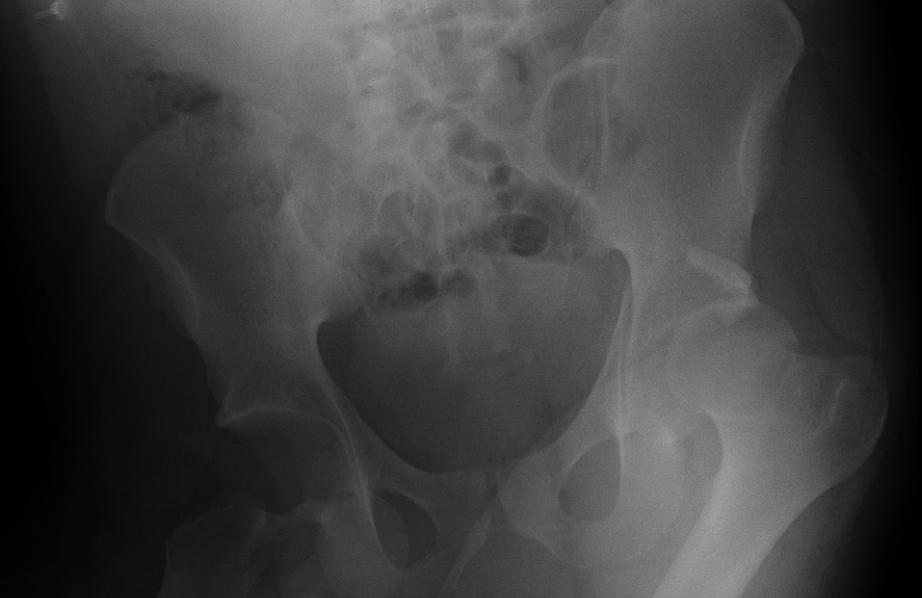

Not So Typical Hip Dislocation

A 20-year-old female presents to the ED after MVC with left hip pain. Notably her leg was up on the dash of the car when the accident occurred. Unable to ambulate since the accident and her pain is constant and worse with attempted movement. She notes muscle spasms around her left hip region. She was lying on the stretcher with the affected lower extremity abducted, slightly flexed and externally rotated without obvious shortening. On log roll testing she reported significant pain especially in the anterior groin region.